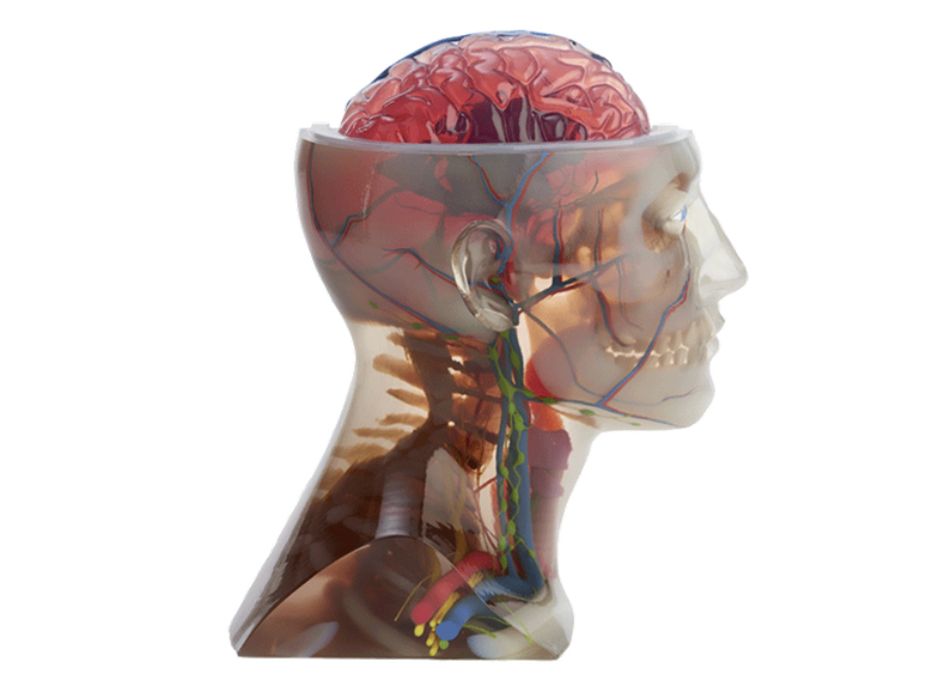

Stratasys Direct Now Offers Anatomical 3D Printing

Stratasys Direct announced new anatomical consulting and 3D printing services.